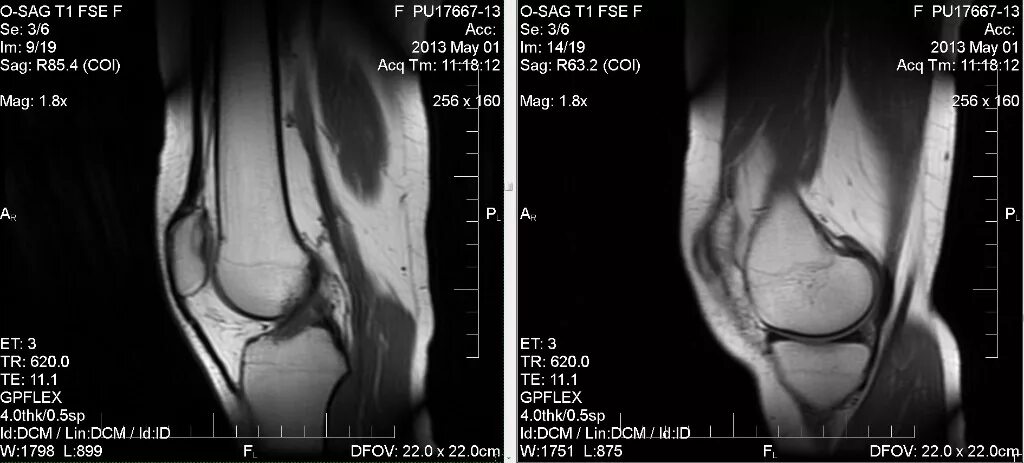

Мрт коленного сустава одежда